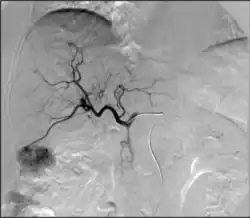

• Angiography: Imaging the blood vessels to look for abnormalities with the use of various contrast media, including iodinated contrast, gadolinium based agents, and CO2 gas.[3]

1. Angiography: Sometimes referred to as traditional angiography, catheter angiography or digital subtraction angiography (DSA). A small needle is inserted into a blood vessel, then exchanged for a catheter over a wire. The catheter is directed at the vessel to be studied, and contrast is directly injected to evaluate the lumen under video X-ray. This is an older technique than modern CT angiography or MR angiography, but provides unique advantages. With a catheter in place, provocative maneuvers can be performed such as breath holds or instillation of vasodilators, to evaluate a patient's blood flow dynamically. This can reproduce symptoms and identify functional abnormalities in a vessel that a static CT or MR imaging cannot.[80][81] Angiography provides the basis for all endovascular therapy.